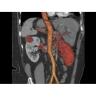

КТ аппарат GE Optima CT520

Современный КТ-аппарат с высокой скоростью сканирования и точной визуализацией. Обеспечивает детализированные снимки для надежной диагностики. Экономичное энергопотребление и удобное управление повышают эффективность работы. Отличный выбор для медицинских учреждений любого уровня.

Современный КТ аппарат GE Optima CT520 – это инновационное оборудование для точной и быстрой диагностики. Он сочетает в себе передовые технологии, надежность и удобство использования, что делает его востребованным в медицинских учреждениях различного профиля.

• Высокое качество изображения благодаря усовершенствованной системе реконструкции данных.

• Сниженная лучевая нагрузка на пациента без потери информативности снимков.

• Широкая область применения: от неврологии до кардиологии и онкологии.